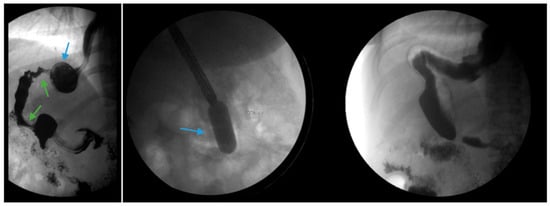

Figure 4.

(Left) An upper gastrointestinal series in a patient post-sleeve gastrectomy with recurrent dysphagia reveals dilation of the gastric sleeve at the cardia (blue arrow) with narrowing and delayed passage of contrast through the middle and distal portions (green arrows) of the gastric sleeve. (Middle) The patient underwent serial endoscopic through-the-scope balloon dilation to 20 mm (blue arrow) with improvement in sleeve stenosis (Right) and dysphagia.

3.4.4. Treatment of Underlying Postoperative Complications: Gastric Sleeve Stenosis

Endoscopic balloon dilation (EBD) has been shown to be a safe and efficacious modality for gastric sleeve stenosis (GSS) (Figure 4) [49,50]. A meta-analysis by Chang et al. of 18 studies involving a total of 426 patients revealed an overall success rate of 76% and an average of 1.8 dilations per patient [51]. Proximal GSS had a higher efficacy rate of 90% compared to distal GSS which had an efficacy rate of 70% [51]. Studies in the meta-analysis utilized through-the-scope, controlled radial expansion balloons, pneumatic balloons used for achalasia or a combination of the two [51]. The optimal balloon type, balloon size and the number of dilations required remains unclear [52]. Fully covered self-expanding metal stents (FCSEMS) have been reported to be effective in 70% of cases in which EBD failed though stent migration remains a concern [51,53].